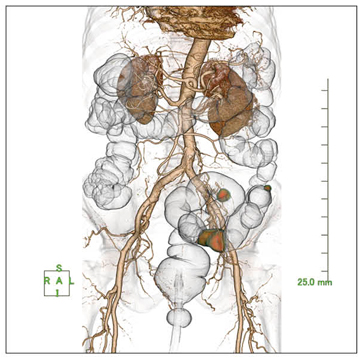

“肝臓解析ソフトウェア”は,肝臓の術前シミュレーションや,術後の経過診断などをサポートするソフトウェアである(図1)。このソフトウェアの目的には,術前シミュレーション,生体肝移植ドナーの肝実質の体積評価,肝実質の血管支配領域推定や血管の抽出,生体肝移植時における肝切除後の機能推定,血管結紮後の肝臓ダメージなどの推定,腫瘍の栄養血管の補助観察などが挙げられる。

機能としては,肝臓実質・下大静脈・門脈・肝静脈などのボリュームを算出し,各血管の肝実質における支配領域をセミオートにて抽出可能である。また,肝右葉・左葉区別や亜区域(S1〜S8)別のボリューム計測も可能で,各区域抽出後は自動的に残肝ボリューム値は引き算され,ユーザーの負担を軽減してくれる。

図1 肝臓解析ソフトウェア